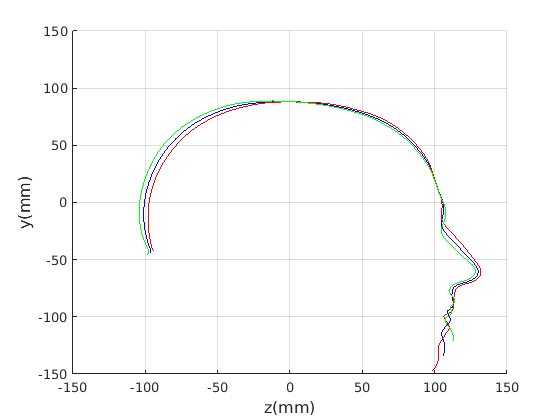

For the cranial sagittal profile model, when not scale-normalised (Fig. 20, left column), the following dominant shape modes are observed:

-

1.

Cranial height variation with a low correlation with cranial length.

-

2.

Cranial length variation with a low correlation with cranial height.

-

3.

A cranial bulge that varies between the front and rear of the cranium.

-

4.

This mode picks up minor variations on cranial shape and some noise where hair exits from the latex cap.

When data is scale normalised (Fig. 20, right column), cranial height and length are more significantly correlated, as shown in the first mode (top right in figure). The second mode model a bulge that can vary from the front to the rear of the cranium. Taken together, these two modes capture close to 90% of the variation in the training set. A two-dimensional model, based on these two modes is used in a clinical case study in Sect. 8.